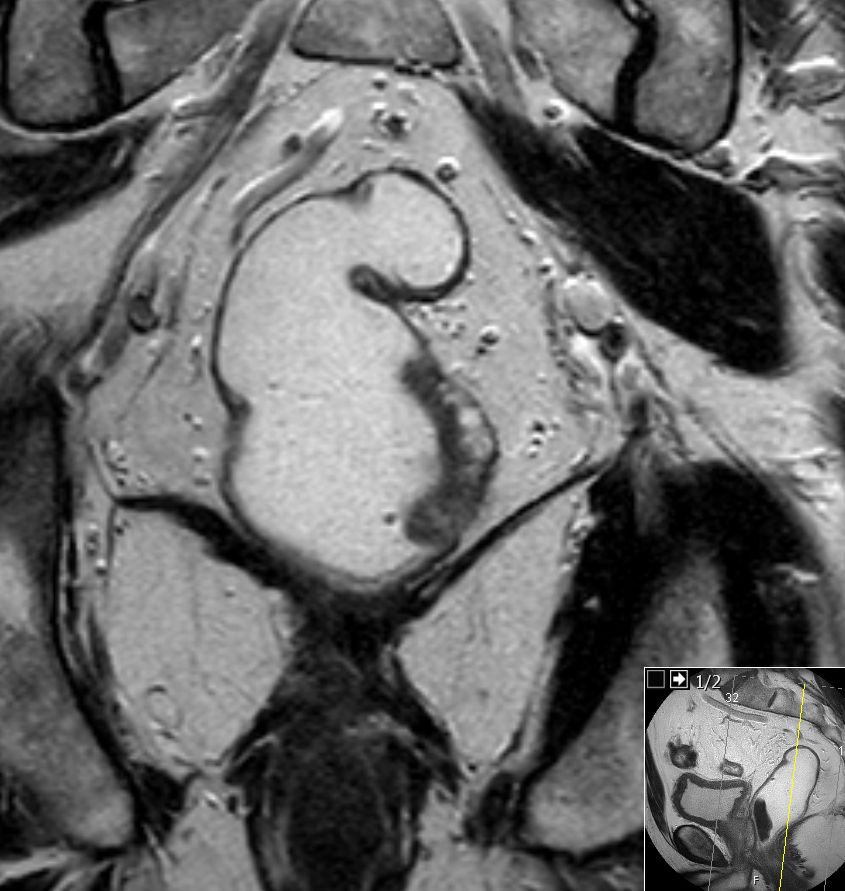

| MRT: T2-Tumor | 61-jähriger Mann mit G2-Adenokarzinom des Rektums von 8-14 cm. T2-Tumor ohne Hinweis auf Wandüberschreitung.![]() |

![]() |